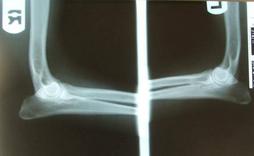

Elbows

Elbows can be x-rayed by any vet, but results should be evaluated by OFA (Orthopedic Foundation for Animals). Proof should be provided.